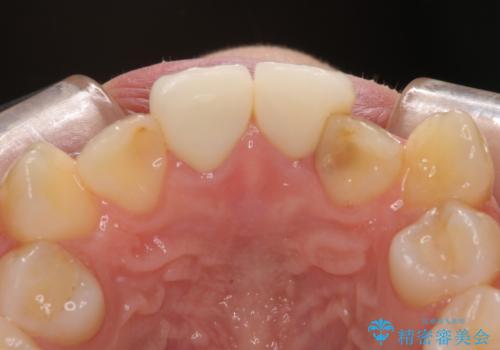

- 学生の頃に神経を取り除いた前歯の変色と、色合いの悪いかぶせ物が気になるとのことで来院された患者様です。

レントゲン写真より、歯根の炎症が認められず、土台もしっかりと植立されていたため、仮歯に置き換えた後にオールセラミッククラウンにて補綴することとしました。